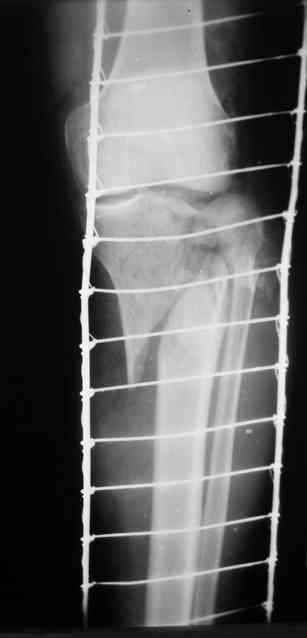

Р-граммы за март и апрель

Р-граммы и фото за 4.05.2007 - 7-е сутки после операции.

Ход операции - линейным разрезом по передней поверхности голени обнажена зона ложного сустава большеберцовой кости. От кости отсепарованы медиально м/ткани. Из зоны ложного сустава убраны рубцовые ткани, мобилизован дистальный отломок. По передней поверхности удалены два осколка, связанных грануляциями. Произведено удаление грануляционной ткани из проксимального отломка (на вид сине-серого цвета), "чистого" гноя не было. Затем произведено наложение аппарата и репозиция отломков. По передне-медиальной поверхности образовался дефект до 4х2х2 см + полость в проксимальном отломке. Удаленные осколки очищены от грануляций, уложены в место дефекта, зажаты между отломками. После иссечения раны по передней поверхности, находящейся рядом с операционной раной, последняя ушита с большим натяжением.

Перелом мыщелка сросся. Проксимальный отломок очень порозный.

На перевязках - из раны небольшое кол-во сукровичного отделяемого. Отек голени умеренный, состояние кожи на фото.